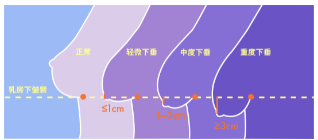

不同程度的胸下垂